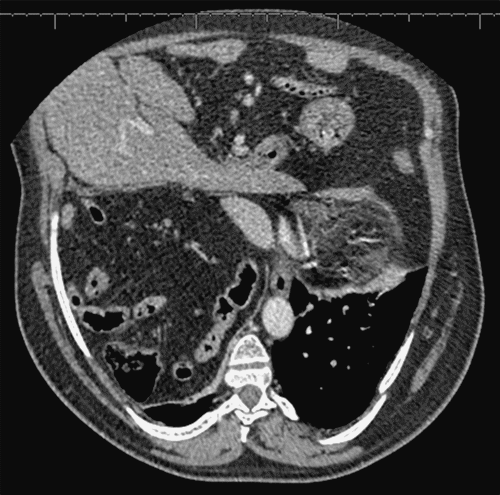

We present the case of a 50-year-old male with a remote history of a repaired left congenital diaphragmatic hernia in infancy and chronic obstructive pulmonary disease requiring 2 liters/minute of supplemental oxygen (with no history of tobacco use). He presented with chronic shortness of breath, dyspnea on exertion, and orthopnea. Pulmonary evaluation led to a chest computed tomography (CT) scan, which revealed an exceptionally large right diaphragmatic hernia containing significant portions of the liver, mesenteric fat, and loops of both small and large bowel herniated into the right hemithorax (Figure 1). He was subsequently referred for thoracic surgical consultation for diaphragmatic hernia repair.

Figure 1. Preoperative CT of Large Right Diaphragmatic Hernia. Published with Permission

Axial views from a preoperative CT scan of the chest and abdomen. Note a large right-sided diaphragmatic hernia with substantial herniation of abdominal contents, including segments of the liver, mesenteric fat, and loops of small and large bowel, into the right hemithorax